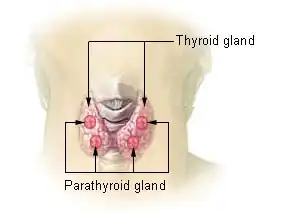

Tireoide e paratireoide

A tiroide (português europeu) ou tireoide (português brasileiro) AO 1990 (do grego θυρεός thyreos "escudo", devido ao seu formato) é uma glândula endócrina dos vertebrados. Em humanos, fica no pescoço e consiste em dois lobos conectados. Os dois terços inferiores dos lobos são conectados por uma fina faixa de tecido chamada istmo da tireoide. A tireóide está localizada na parte frontal do pescoço, abaixo do pomo de Adão. Microscopicamente, a unidade funcional da glândula tireóide é o folículo esférico da tireóide, revestido por células foliculares (tireócitos) e células parafoliculares ocasionais que circundam um lúmen contendo colóide. A glândula tireoide secreta três hormônios: os dois hormônios da tireoide - triiodotironina (T3) e tiroxina (T4) - e um hormônio peptídico, a calcitonina. Os hormônios tireoidianos influenciam a taxa metabólica e a síntese protéica e, em crianças, o crescimento e o desenvolvimento. A calcitonina desempenha um papel na homeostase do cálcio.[1] A secreção dos dois hormônios da tireoide é regulada pelo hormônio estimulante da tireoide (TSH), que é secretado pela glândula pituitária anterior. O TSH é regulado pelo hormônio liberador de tireotropina (TRH), que é produzido pelo hipotálamo.[2]

A tireoide está perto da parte frontal do pescoço, apoiada e em torno da parte frontal da laringe e traquéia.[5] A cartilagem tireóide e a cartilagem cricóide ficam logo acima da glândula, abaixo do pomo de Adão. O istmo se estende do segundo ao terceiro anéis da traquéia, com a parte superior dos lobos estendendo-se até a cartilagem tireóide e a parte inferior em torno do quarto ao sexto anéis traqueais.[7] Os músculos infra-hióideos situam-se à frente da glândula e o músculo esternocleidomastóideo ao lado.[8] Atrás das asas externas da tireoide estão as duas artérias carótidas. A traquéia, a laringe, a faringe inferior e o esôfago ficam atrás da tireoide.[6] Nessa região, o nervo laríngeo recorrente[9] e a artéria tireoide inferior passam próximos ou no ligamento.[10] Normalmente, quatro glândulas paratireoides, duas de cada lado, situam-se em cada lado entre as duas camadas da cápsula da tireoide, na parte posterior dos lobos da tireoide.[5]